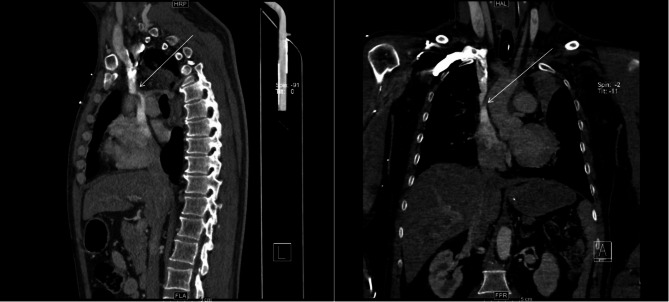

Case presentation: We report the first case of SVC syndrome in an adult patient with pre-existing SVC angulation, exacerbated by cannula placement during VV ECMO therapy. Serial venous-phase chest CT scans (pre-ECMO and during ECMO support) demonstrated progressive luminal narrowing at the cannula tip site, correlating with clinical manifestations of SVC obstruction. The patient was successfully weaned from VV ECMO, achieved complete resolution of SVC syndrome symptoms, and was discharged without neurological sequelae.